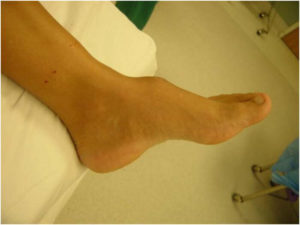

- некоторые инфекционные заболевания (например, сифилис). На фото экзостоз пяточной кости

- голеностопный сустав;

Экзостоз можно выявить во время осмотра и ощупывания подозрительных участков на стопе, голени, руке, ключицах. Недуг развивается постепенно и может никак себя не проявлять в течение долгого времени.

Болевые ощущения могут появиться лишь тогда, когда нарост будет давить на ближайший сосуд или нерв. Иногда костяные и хрящевые наросты обнаруживаются случайно, во время рентгена. Рентгеновское обследование дает развернутую информацию о виде и форме нароста, о его размерах степени развития.

Нужно помнить, что на снимке рентгена хрящевой ткани новообразования не видно. Из-за этого нарост на фото всегда меньше, нежели в реальности.